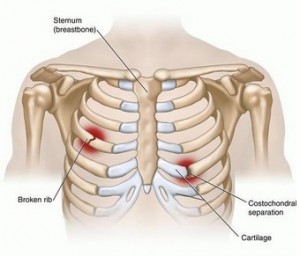

How to diagnose broken ribs. The doctor will first give you an exam to look. If you have a broken rib, symptoms such as bruising, pain and swelling are considered very Press on the injured area.

A broken rib typically causes sharp pain. To diagnose a rib injury, it’s best to see a medical professional who can look at your injuries with professional tools and technology. You may also feel or hear a crack or pop when the.

Sometimes, you may be able to feel a break in your rib by rubbing your finger over the rib. If you have a tender area on your ribs that hurts with every breath, you may have a broken rib. If you heard cracking during the injury or you hear or feel cracking when you move or.